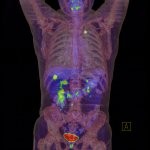

A PET/CT nem más, mint egy PET (pozitron emissziós tomográf) és egy CT (computer tomográf) kamera együttes munkája. A PET kamera működése során a vizsgálat előtt szervezetbe juttatott izotópos nyomjelző anyag bomlása során kibocsájtott pozitronokat érzékeli, amik a sejtek anyagcsere-folyamatait ábrázolják, míg a CT a szervezet anatómiai tulajdonságait ábrázolja. A két kép egymásra vetüléséből jön létre a PET/CT felvétel, ahol pontosan lokalizálható minden elváltozás, amit a PET kamera érzékelt.

59 éves úriember jelentkezett intézetünkbe korai diagnosztikára tünet-és panaszmentesen. Az elvégzett egésztest PET/CT vizsgálat során a vastagbél utolsó szakaszában egy 1 cm-nél kisebb, kóros cukorhalmozást észleltünk a bélfalban. Ennek alapján vastagbél tükrözéses vizsgálatot javasoltunk az úrnak, amin ő részt vett, és a beavatkozás során egy 1 cm körüli kis polipot távolítottak el a vastagbél belső felszínéről. Ennek a szövettani faldolgozása sajnos olyan eredményt hozott, hogy itt, ebben a kis polipban egy rosszindulatú daganat van. Mivel a követő, későbbi kolonoszkópiákkal (vastagbéltükrözéssel) már nem sikerült azt a helyet azonosítani, ahonnan ezt eredetileg eltávolították, a betegnek a követő PET/CT vizsgálatok tudták csupán azt bizonyítani, hogy a daganatnak nem alakult ki helyi kiújulása vagy távoli áttéte.